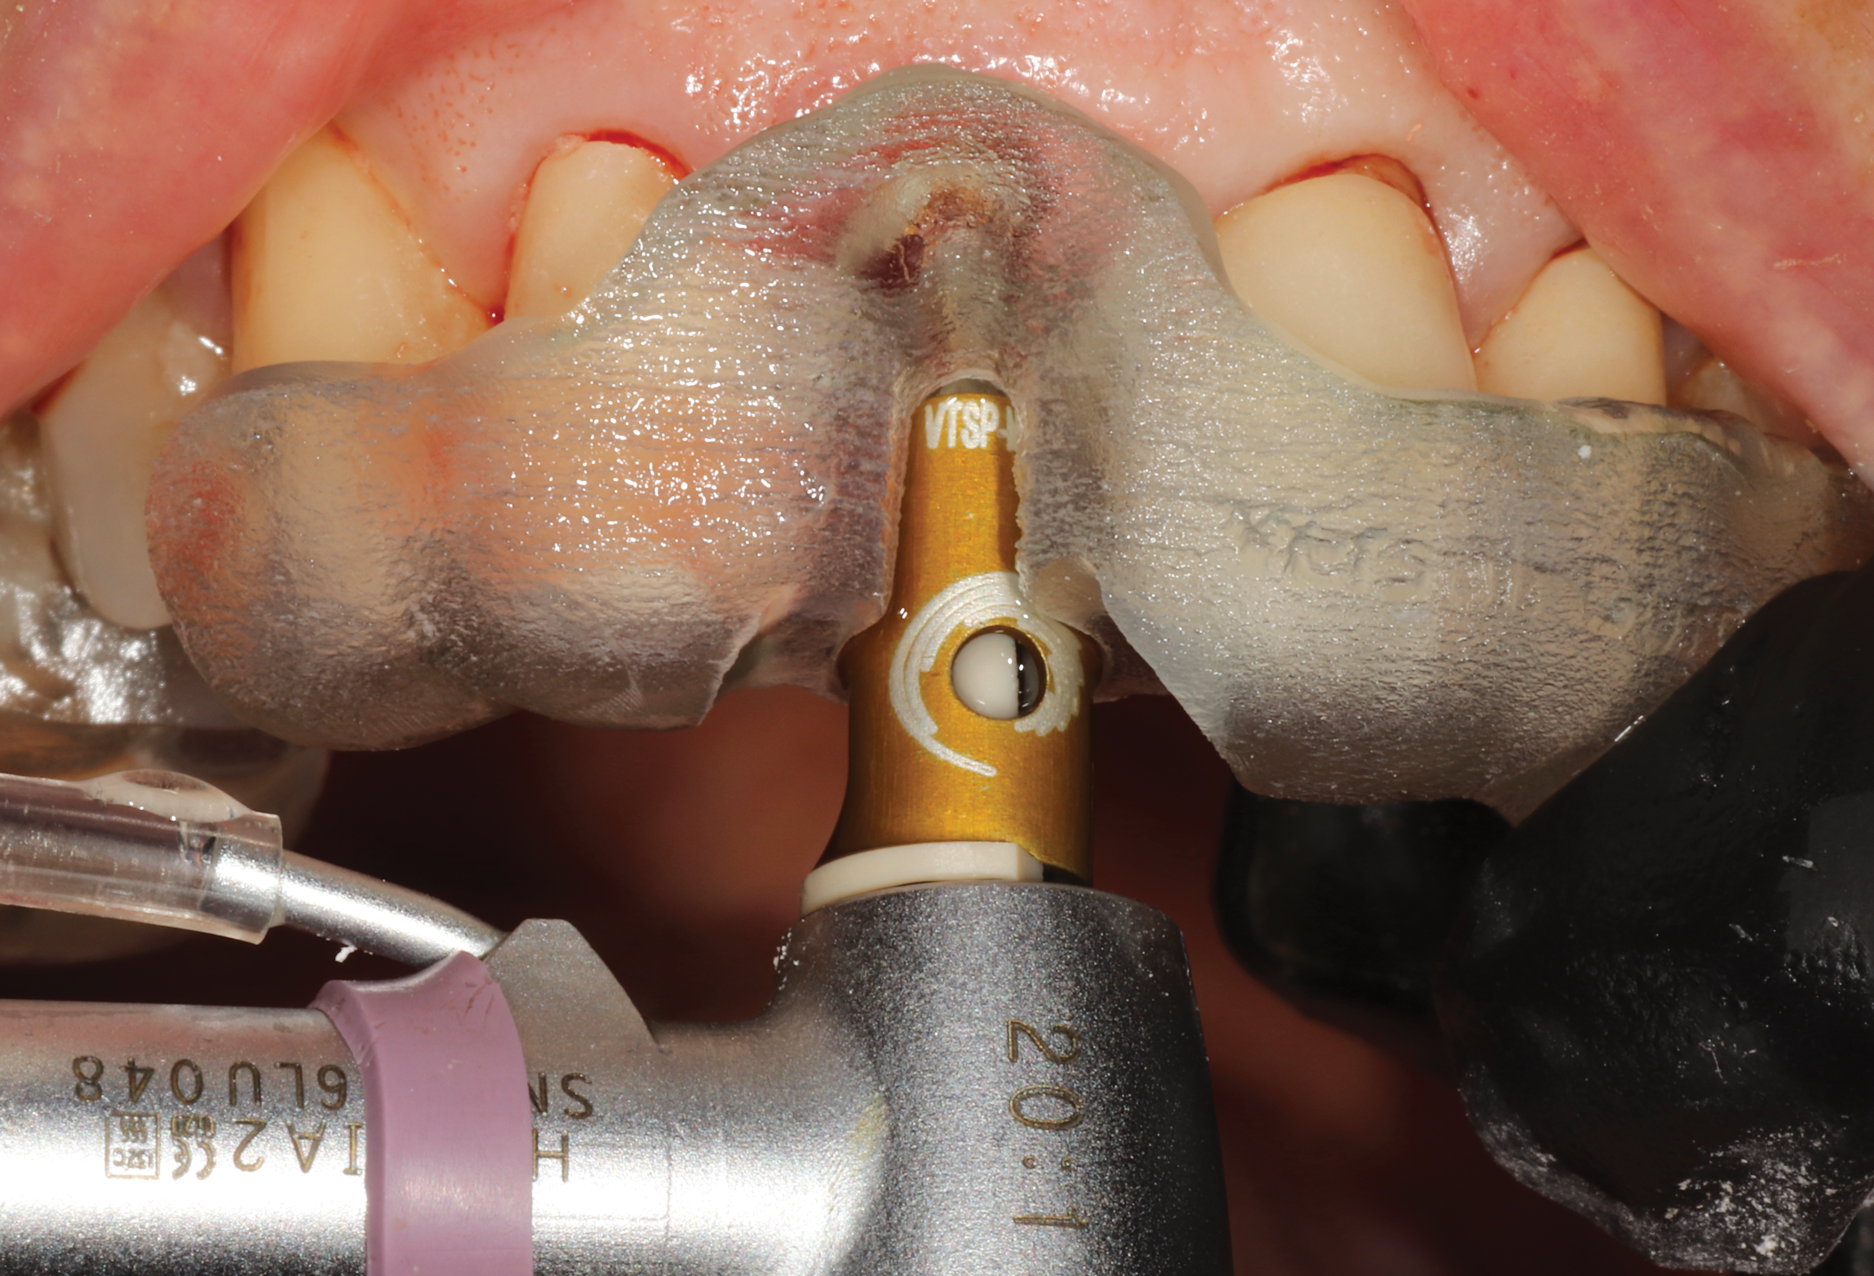

Using the TAP method for calibration, the existing implants were used as markers for the navigational unit (Figure 11). Full-thickness flaps were elevated on both planned implant site locations. Pilot drills and all subsequent drills were calibrated for navigational surgery. Two implants were placed with adequate torque of 40+ Ncm and ISQ values of 80 and 79, respectively, enabling second staging of implants with healing abutments (Figure 12). The surgical sites were sutured and allowed to heal.

Fig 11. Trace and place (TAP) technique utilizing existing implants

as radiographic markers.